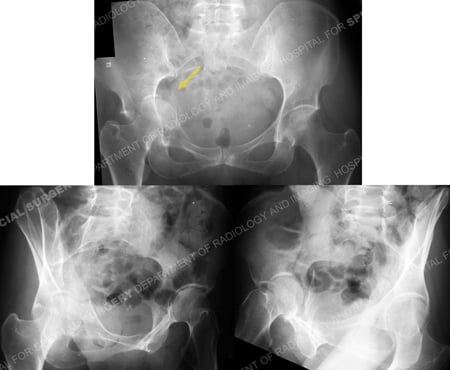

Radiographs demonstrating a right-sided Anterior Column acetabular fracture with displacement of the quadrilateral surface and medial femoral head protrusion (arrow).